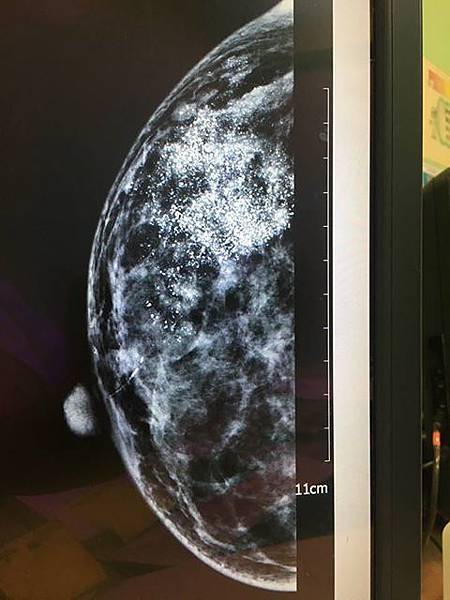

<<乳房X光攝影 v.s. 乳房超音波>>差異比較

乳癌是女性最常見的癌症,雖然乳癌初期的預後良好,但若能早期發現、早期治療,才更能有效控制病況!阮綜合醫院乳房外科劉宗瑀醫師表示,建議女性及早養成每月自我檢查的習慣,45歲以上婦女則建議每兩年接受乳房X光攝影,若發現疑似病灶可搭配以乳房超音波進行診斷或切片檢查,以對腫塊進行診療評估。

<<不可不做的超重要乳房攝影~~介紹微鈣化>>